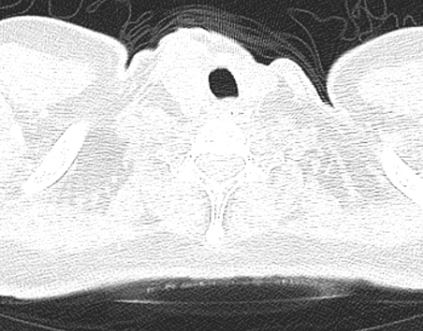

气管里一大个肿物,普通CT平扫为什么漏诊?

图1~图2

图3~图4

图5~图9